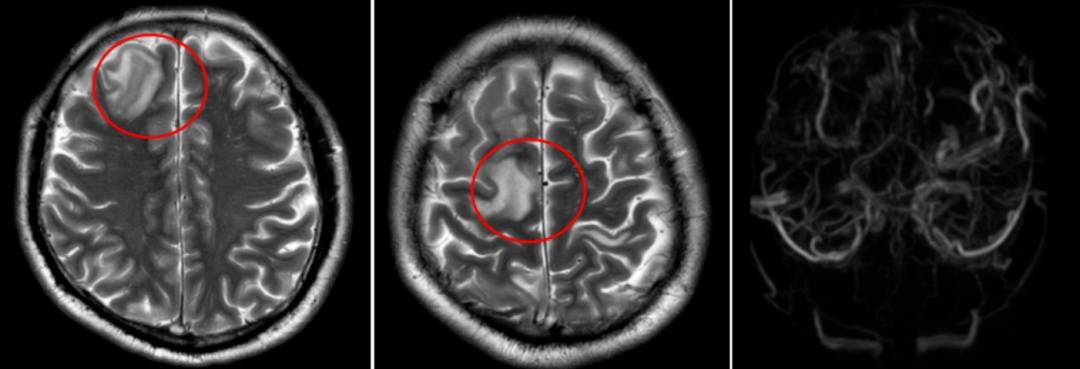

该院神经内二科医生陈婉洁接诊后,高度怀疑静脉窦血栓形成,紧急安排了相关检查。结果显示:右侧颈内静脉、双侧乙状窦、横窦、窦汇、上矢状窦多发血栓,伴静脉淤积性脑梗死。

患者头颅磁共振检查

“脑静脉窦血栓形成是一种相对罕见的中风类型,发病率虽不高,但后果严重。”钟水生用通俗的语言解释说,大脑里有一套“排水系统”——脑静脉和静脉窦,负责清除代谢废物、调节颅内压力等。正常情况下,血液流动顺畅,大脑“排水”正常。一旦形成血栓,静脉回流受阻,大脑“排水”异常,形成颅高压、静脉淤积性脑梗死或出血,引发头痛、呕吐、四肢抽搐、视物模糊、一侧肢体无力或麻木、意识模糊等症状,严重时甚至形成脑疝,危及生命。